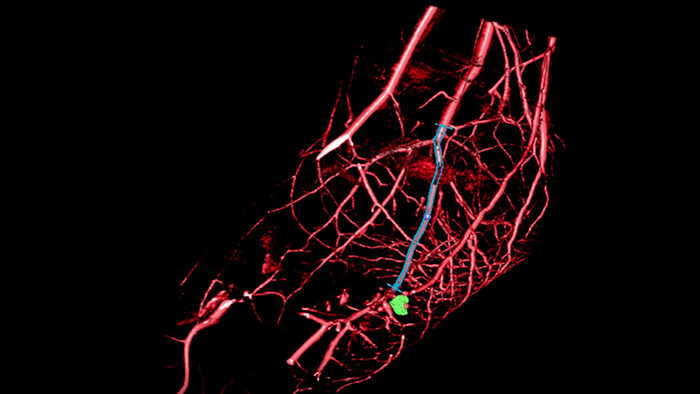

SmartCT Roadmapは、ライブ3D画像オーバーレイ機能を備え、画像をセグメンテーションして対象となる血管と病変を強調できます。SmartCT Roadmapでは血管全体、セグメンテーションされた血管、アノテーションの3D再構成画像をライブの透視像と併せてオーバーレイします。これにより3D画像の透明度とコントラストが得られ、詳細部の視認性が向上します。